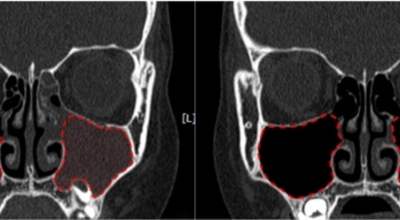

외과적 치료

내과적 치료에 반응하지 않는 만성 부비동염의 경우 수술 치료가 필요합니다.

첫째, 자연공을 통한 부비동의 배액과 환기 유지입니다. 둘째, 발병의 선행 요인인 비강 내 구조적 이상을 제거하던가 교정하는 것으로 보입니다. 셋째, 부비동 점막의 병변이 비가역적이라면, 부비동 점막을 없애는 것으로 보입니다. 보통은 부비동 내시경 수술을 시행합니다.

일부 환자에게는 풍선카테터라는 부비동 수술을 시행합니다. 수술 전에 부비동의 염증을 치료함으로써 분비물의 배액을 막는 자연공의 점막 부기를 줄이고, 부비동에 저류된 분비물의 배액을 재촉해니다. 섬모의 기능을 촉진하고 치료 중이나 치료 후에 자연공의 소통을 유지시킬 수 있는 내과적인 치료를 하시는 게 좋겠습니다.